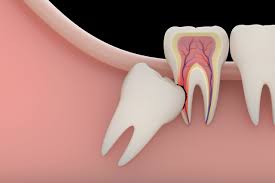

1. When impacted wisdom teeth grow, they injure adjacent teeth. The dental nerve becomes infected and inflamed, causing severe pain. The dental nerve dies, and the periodontium may be sealed.

2. When impacted wisdom teeth grow, the roots of adjacent teeth are squeezed and broken, and the dental nerves become infected and inflamed, causing severe pain. The adjacent teeth cannot be reworked and can only be extracted.

3. A deep blind pocket will be formed between the impacted wisdom teeth and the surrounding gums, which can easily cause food residues to stick to the tooth surface, thereby accumulating for a long time, gradually forming bacterial infection, and deep caries can reach Deep in the dentin, close to the pulp, or may have affected the pulp, causing severe pain.